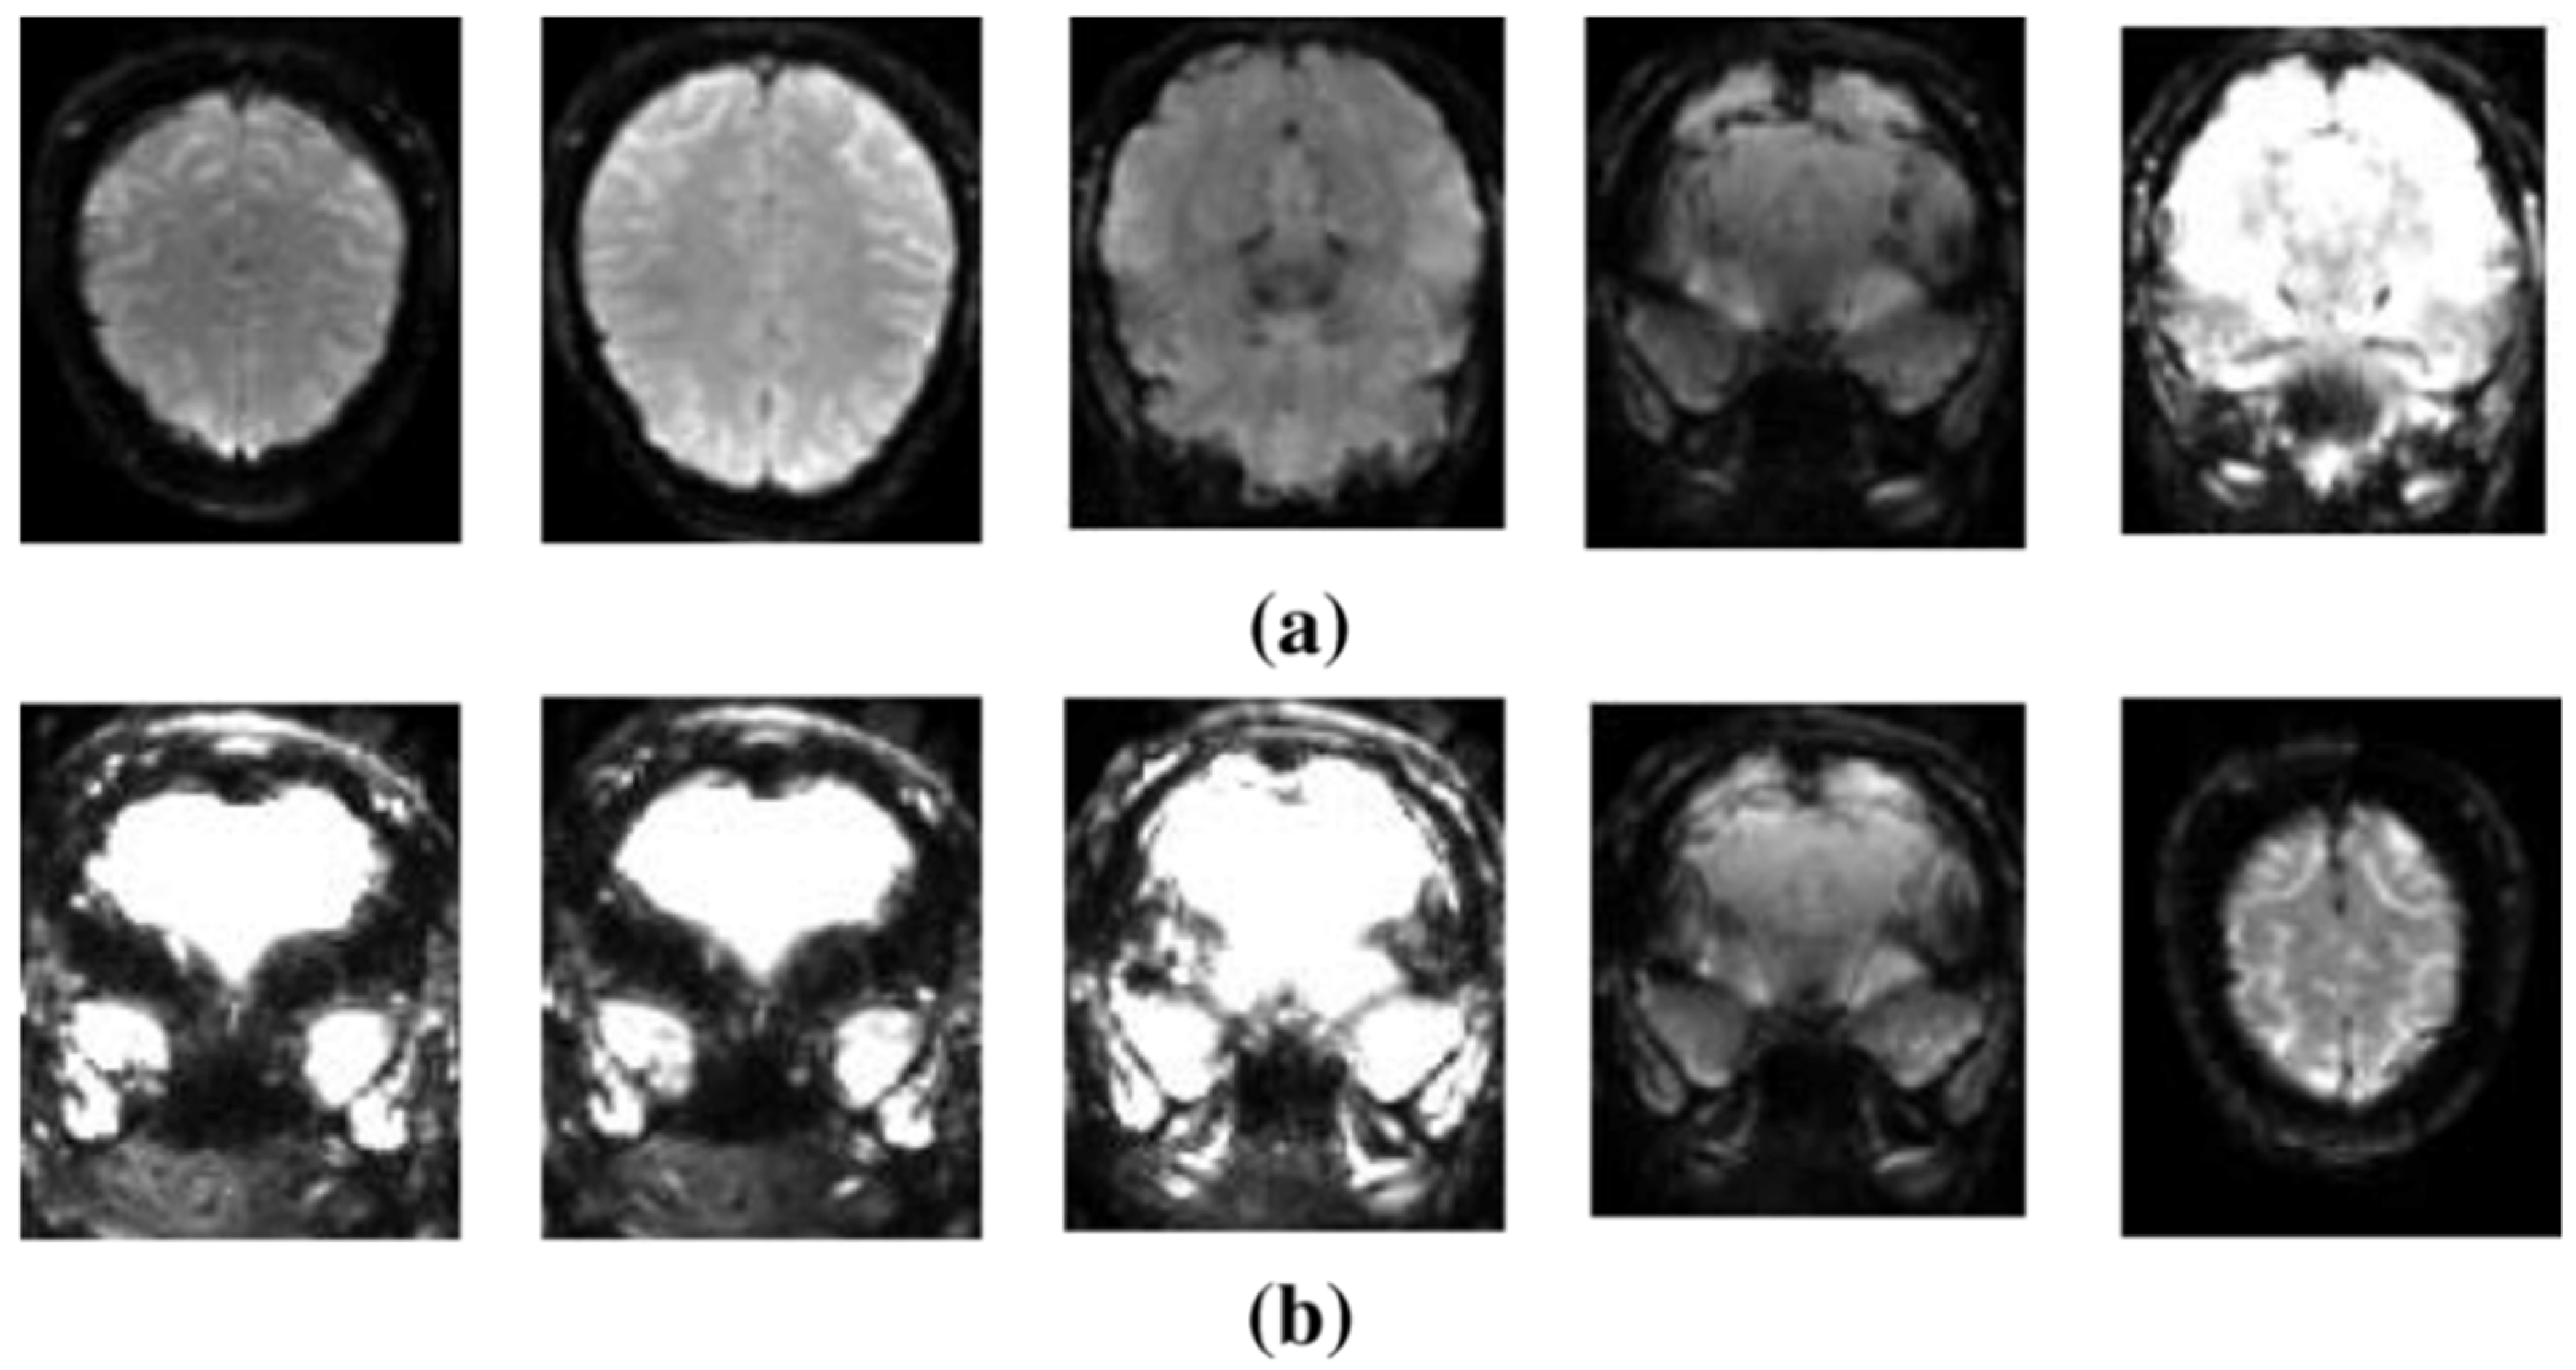

4.2. sMRI-Based Diagnosis of SZ

- SZ is linked to modest structural abnormalities in the brain, such as variations in gray-matter volume and cortical thickness. These modifications might vary greatly between individuals, making it difficult to create models that accurately capture these differences. More complex models can be built using advanced ML techniques and larger datasets.

- Most sMRI investigations are cross-sectional, capturing brain structure at a single point in time. Longitudinal studies that track structural changes over time are required to better understand the course of SZ. These investigations can shed light on how brain structure changes over time and aid in the identification of early illness biomarkers.

- Combining sMRI with functional data from fMRI or EEG can help provide a more complete picture of SZ. However, effective integration strategies are still being developed. Multimodal techniques can assist in establishing the link between anatomical abnormalities and functional problems in SZ.